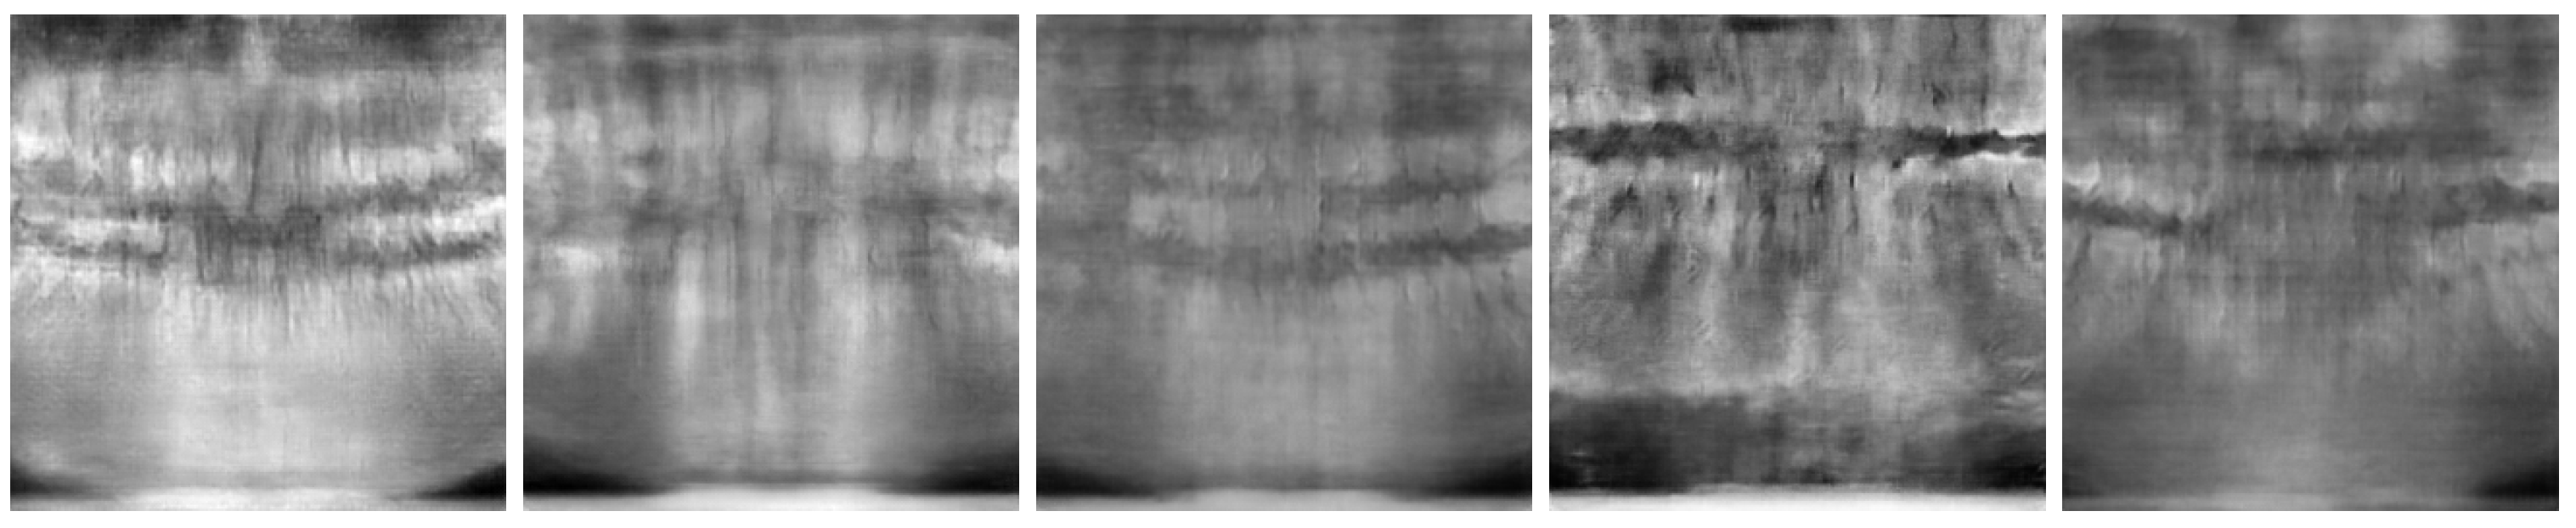

Figure 6 and Figure 7 show the best and worst generated images, respectively, as determined by the average scores for all twelve criteria. The best images show a reasonable depiction of both the overall morphology and certain details, although not at the level of contemporary real-world panoramic radiographs. The worst images display various issues, including poor overall image quality and manifestations of extra rows of tooth crowns.

Figure 7.

Worst images among all model variants, showing poor overall anatomical depiction and severe artifacts.